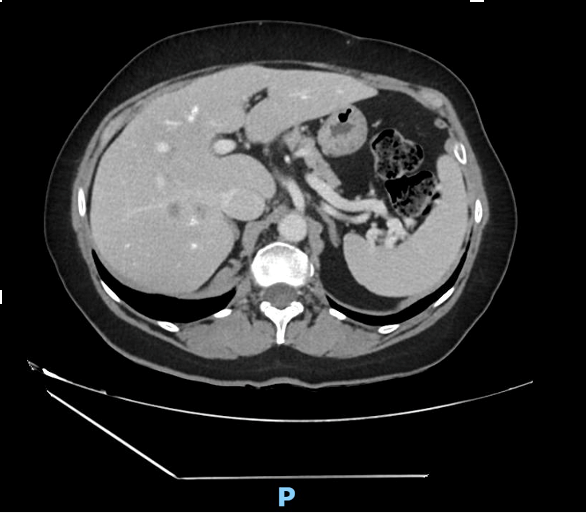

Panoramic imaging was subsequently performed: a CT scan followed by MRI confirmed the suspicion of malignancy, without evidence of biliary dilatation or vascular invasion (Figs. 3 and 4); however, a definitive diagnosis could not be established.

Prostate-specific membrane antigen (PSMA) PET was also performed, and findings were more consistent with hepatocellular carcinoma (HCC).